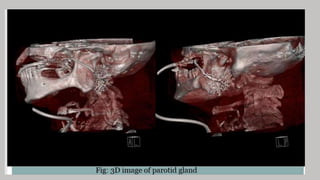

CT sialography

• CT is now well recognized and is of particular value in

distinguishing between lesions within two deep pole of the parotid

and with extrinsic pharyngeal masses which compress and displace

the gland

• Ultrafast CT and three dimensional –image CT sialography have

been effective for visualization of masses

• The disadvantage of CT includes radiation exposure, administration

of the contrast media for enhancement, and potential scatter from

dental restorations.